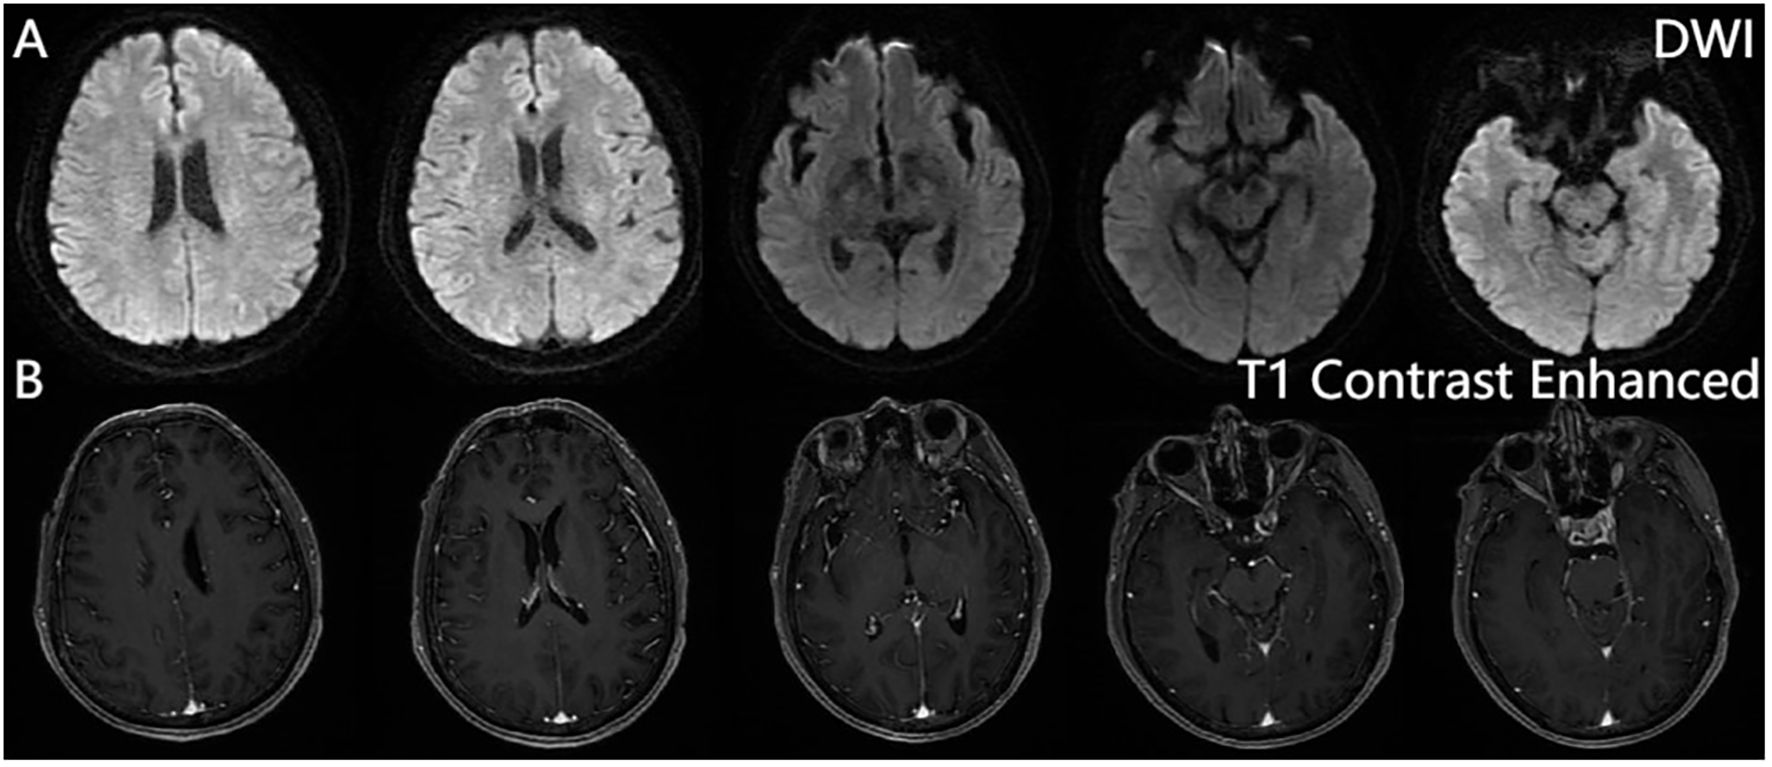

Figure 3

MRI brain scans showing axial slices. The top row displays Diffusion Weighted Imaging (DWI) scans, depicting various brain structures in grayscale. The bottom row presents T1 contrast-enhanced images, providing enhanced detail of the same brain structures, also in grayscale.

Figure 3. Brain magnetic resonance imaging. Diffusion-weighted imaging (DWI) (A), contrast-enhanced sequences (B). No significant hyperintensity is observed on DWI, and post-contrast sequences reveal no abnormal enhancement in the brain parenchyma, calvarium, or meninges.